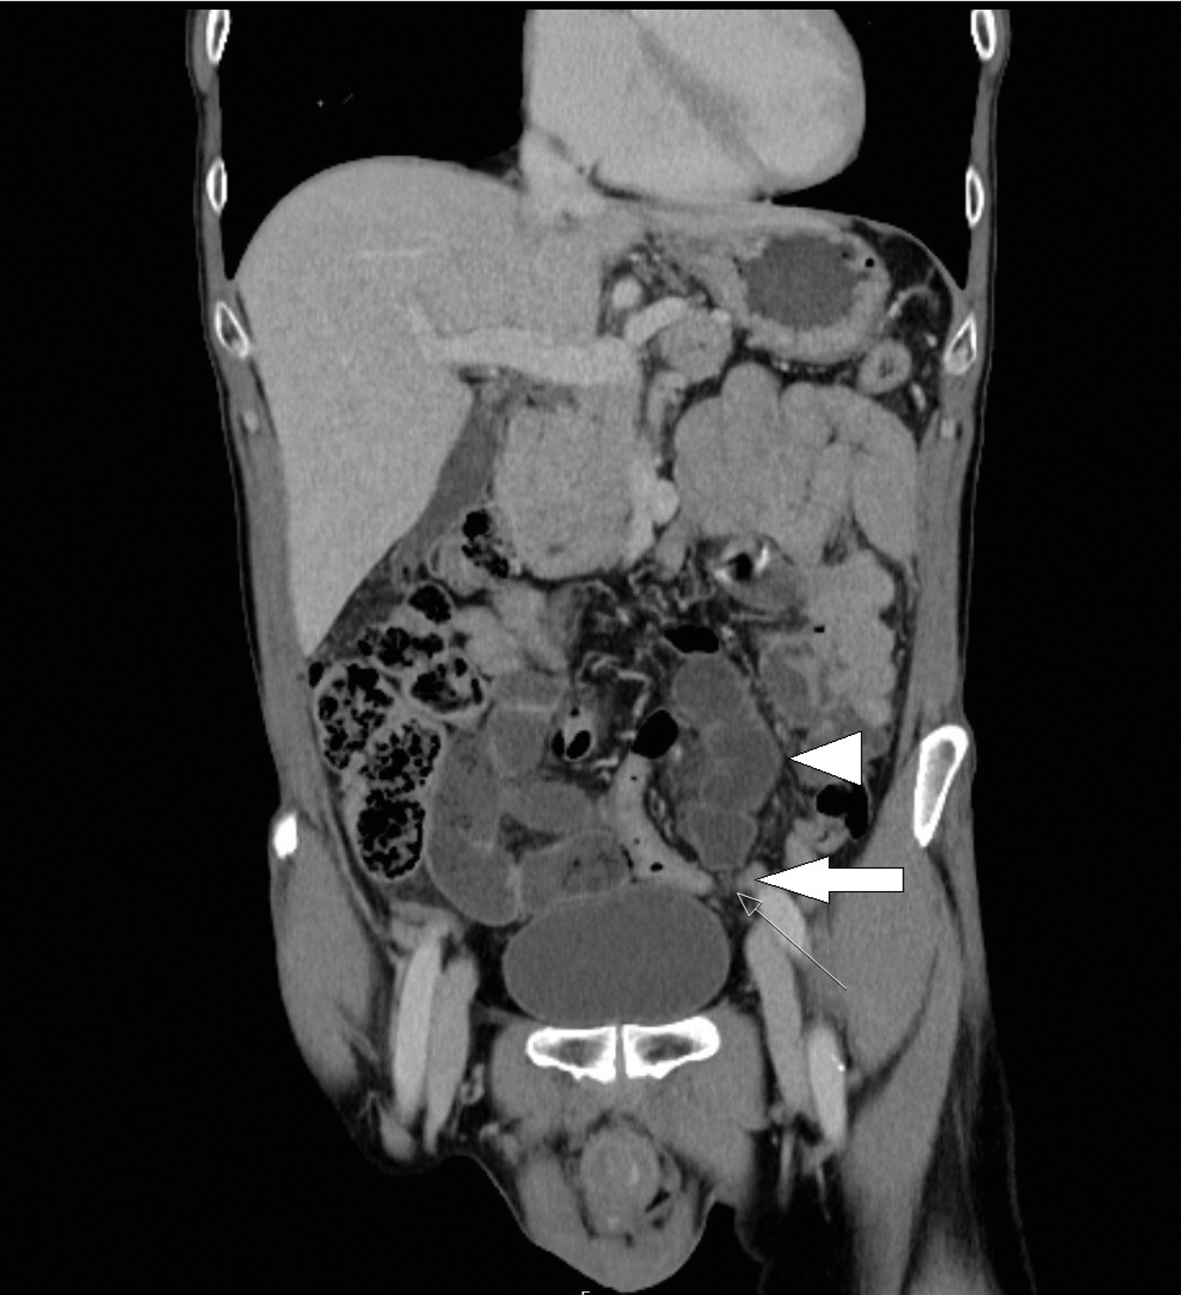

En man i 50-årsåldern sökte till akutmottagningen med några timmars anamnes på kraftig låg buksmärta som debuterat plötsligt. På akutmottagningen hade patienten konstant smärta som förvärrades i intervaller. Patienten kräktes upprepade gånger; kräkningarna var utan blod eller kaffesumpsliknande innehåll. Undersökande läkare konstaterade att patienten i övrigt var frisk med en smal kroppskonstitution. Han hade i tonåren genomgått en appendektomi, och ett ärr sågs över höger fossa. Statusmässigt återfanns en uppspänd, tympanisk och ömmande buk med tarmljud. Via akutmottagningen gjordes en datortomografisk röntgenundersökning med kontrast som visade en bild som vid tunntarmsileus med tunntarmsdilatation på 3–4 cm och gas-/vätskenivåer. Orsaken såg ut att vara adherenser mellan tunntarmsslyngor i lilla bäckenet (Figur 1).

Figur 1. Frontal datortomografisk bild med vidgade tunntarmar (pilhuvud) och adherenser i lilla bäckenet (pil). Bild som vid tunntarmsileus orsakad av brid.